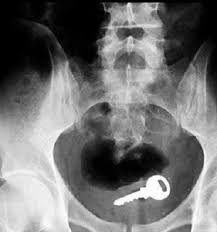

Röntgen filmlerinden “akıl almaz şeyler Hastane koridorlarına düşenler bilir… Doktora görün, tahlilleri yaptır, röntgenleri çektir falan filan derken sayılmadan yaşam gider. Gelin ki bu sefer ilginç şeyler çıkmış ki görün ağzımız açık kaldı..

O Şişe Oraya Bakın Nasıl Girmiş…Röntgen filmlerinden çıkan akılalmaz şeyler Röntgen filmlerinden “akıl almaz şeyler Hastane koridorlarına düşenler bilir…